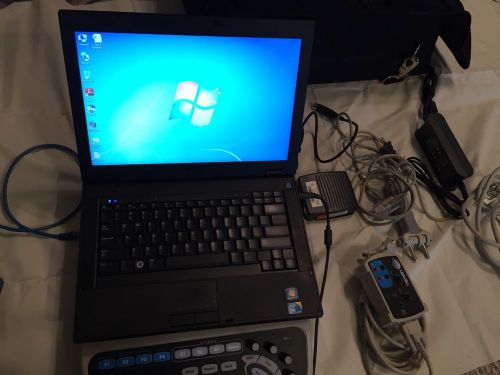

Cadwell Sierra Wave EMG/NCV machine/Window 7 Professional